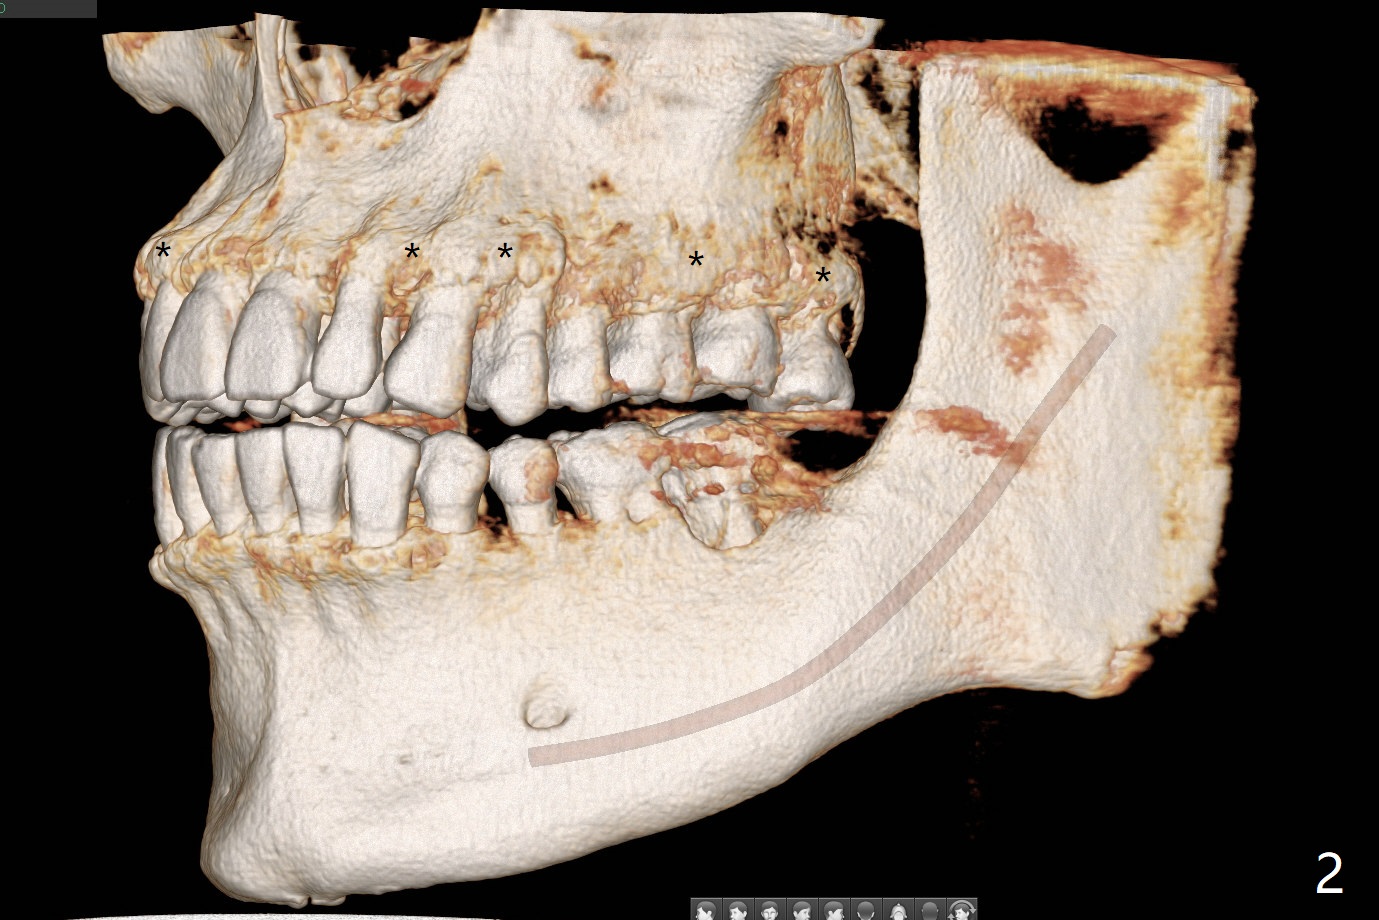

Mesial Root Fracture

A 35-year-old man has repeated pain at #18 (Fig.1). He is a bruxer with exostosis (Fig.2 *). It appears that the mesial root of the affected tooth has vertical fracture (Fig.1-4). A 5x11.5 or 13 mm implant is appropriate (11 or 13 mm FC, Fig.5). Draw blood for PRFx2/sticky bone.